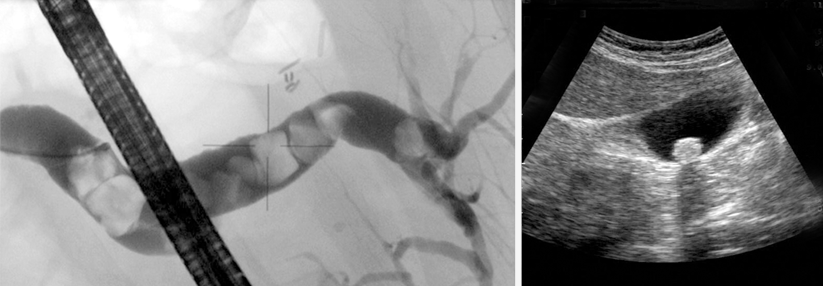

Erscheint die echoendoskopische Entfernung der Gallengangsteine möglich, wird zunächst das Papillenostium dargestellt, sondiert und Galle aus dem Gallengang aspiriert. Anschließend kann unter endoskopischer Kontrolle die Papillotomie erfolgen. Die Steine werden über den vorher in den Gallengang eingebrachten Führungsdraht mit einem Ballonkatheter, seltener mit einem Dormia-Körbchen, entfernt.

Bei der ERC mittels Echoendoskop wird die Papilla duodeni major per Papillotom sondiert und gespalten. Mit einem Draht (links oben im Bild) wird der Stein anschließend extrahiert. Bei der ERC mittels Echoendoskop wird die Papilla duodeni major per Papillotom sondiert und gespalten. Mit einem Draht (links oben im Bild) wird der Stein anschließend extrahiert. © Leineweber T. Hamburger Ärzteblatt 2018; 72: 30-32 © Hamburger Ärzteverlag, Hamburg